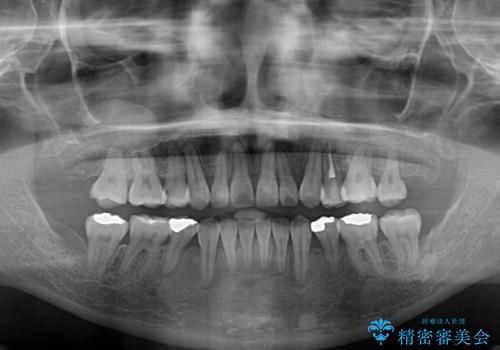

【モニター】上下の八重歯を治したい ワイヤー装置による矯正治療

- 上下前歯のデコボコを気にして来院された患者様です。

デコボコが強いため、非抜歯で矯正をすると出っ歯仕上がりとなるため、上下左右の第一小臼歯4本を抜歯することとしました。

治療期間全体を通して歯の移動スピードがゆっくりであったので、当初予定よりも1年ほど長い、3年間を要することとなりました。